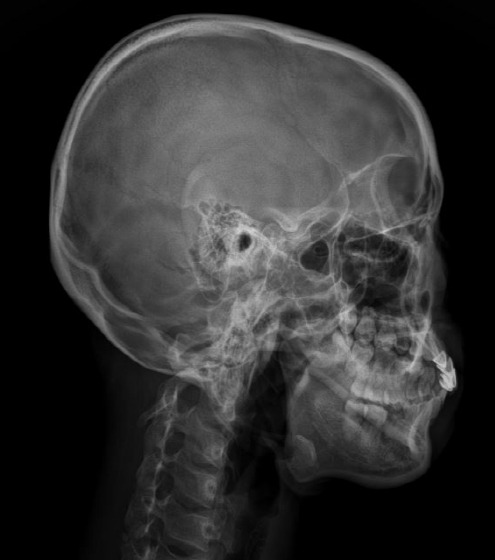

air는 엑스레이에서 까맣게 보여요

위 사진의 두 환자 분의 경우 두개안면골의 비틀림을 재정렬해주는 것만으로도 비중격이 위치가 개선되고 비강 내 공기의 흐름이 좋아진 것을 관찰할 수 있습니다.